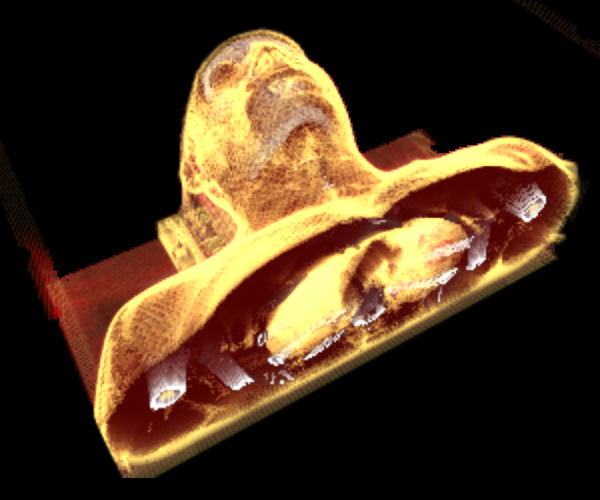

Rendering CT Scans

I mapped the scan's CT density to body tissues (bones, cartilage, muscle, fat, skin) assigning color/transparency to each tissue type.

WebGL Translucency Rendering

When WebGL first came out, I did a weekend project to test tissue color/alpha mapping - and evaluate WebGL performance. I rendered CT scan slices as texturemap planes (billboards), resulting in the expected gap band artifacts you can see along the side view.To support translucency, the slices must be rendered in back-to-front order. I avoided sorting slices by using model-view orientation to determine which slice is to the right of the eye view, then using a reversed slice list on the other side.

My follow-up project was a ray casting iPhone app to display CT and MRI scans.

Optimized Ray Casting

My innovations for this project were to create a new ray casting algorithm that works both back-to-front and front-to-back for optimized translucency, develop tissue segmentation classifiers, and to generate a normal map from tissue segments.I also created a fast algorithm for determining how many rows and columns are in texturemaps, to support user-supplied images with no metadata.

The app renders 2D grayscale CT/MRI scans into 3D color in real-time. Through real-time segmentation, I'm able to filter/display selected body materials. Here's a video of the app: